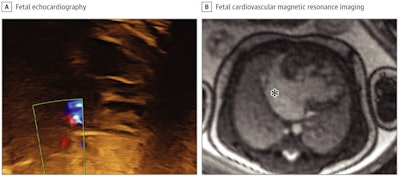

Congenital heart defects are typically identified in utero by echocardiography, but sometimes that modality proves inconclusive due to inadequate acoustic windows. In recent years researchers have developed an MR-compatible Doppler ultrasound device that allows for the acquisition of high-resolution fetal cardiovascular MR (CMR) images without postprocessing.

Salehi and colleagues sought to investigate the efficacy of fetal CMR after inconclusive echocardiography, as well as whether its use resulted in any patient management or parental counseling changes. The team conducted a study of 31 fetuses referred for cardiovascular MRI at Skåne University Hospital in Lund between January 2017 and June 2020; fetuses had a median gestational age of 36 weeks.